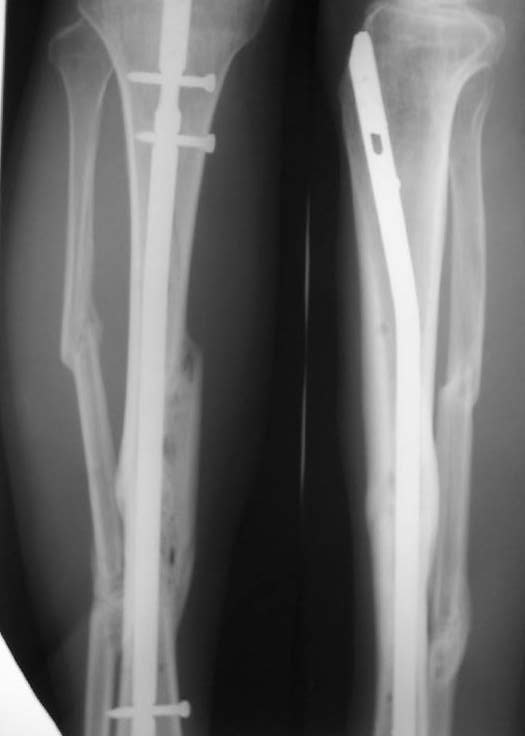

Александр Николаевич, к сожалению больной не является на контрольные осмотры. Я последний раз видел больного, когда прошло 7 месяцев после операции БОС. У него все хорошо. Каких либо жалоб и ограничений в нагрузке нет. Высылаю снимки до операции и последние снимки.